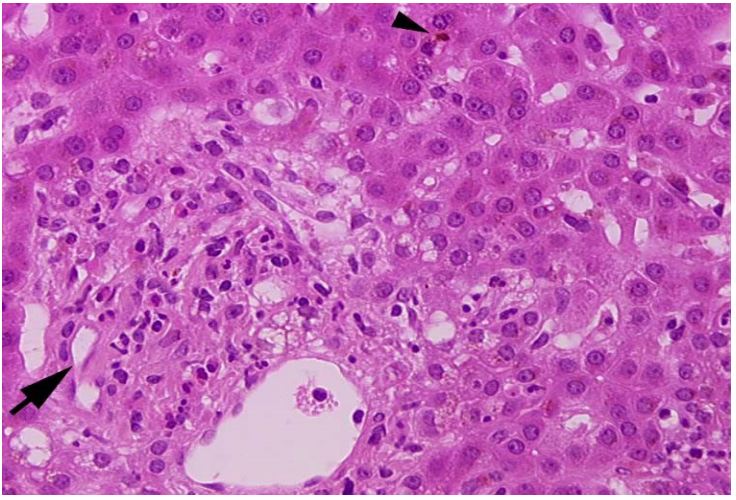

Figure 1: Patient n°1: enlarged portal tract infiltrates with numerous plasma cells (arrow head) and eosinophils, surrounding a damaged bile duct (arrow).

Figure 2: Moderate portal inflammation mainly constituted of eosinophils; bile duct (arrow) was destroyed by the infiltrate and canalicular cholestasis was marked (arrow head).